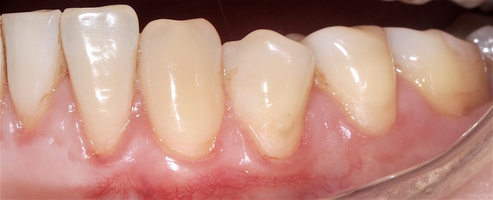

Во всех случаях применения аутотрансплантата и ТМО (dura mater) наблюдается сопоставимый положительный клинический результат по всем параметрам оценки рецессий десны (табл. 4). В случае нескольких зубов в области наиболее глубоких рецессий с наименьшими клиническими показателями имеет место сохранение класса рецессии не более первого класса (9 зубов) и глубиной не более 2 мм, 1.6 зуб — 3 мм.

В зарубежной литературе встречается также совокупный показатель эффективности лечения рецессий десны — процент закрытия корня зуба — отношение разница между конечным и исходным значениями глубины рецессии к исходному значению в процентах. Положительный результатом лечения является значение равное или более 80% [4]. Использование только показателя глубины рецессии десны для анализа эффективности лечения без учета остальных показателей (ТКД, ШКД, РРД, ЗДК) не дает полной картины результата и может быть применимо только в совокупности с другими показателями (рис. 6а-й).

Так в нашем случае процент закрытия корня зуба наблюдается больше 80% у 13 зубов. Менее 80% — у 11 зубов. Это связано с сохранением класса рецессии после лечения в области зубов с наибольшим классом рецессии и наибольшим показателем глубины рецессии. При этом средний показатель всех 24-х оперированных зубов — 83,1%. При этом среднее значение процента закрытия корня зуба для зубов с положительным результатом (более 80%) составляет 96,65%. Среднее значение для результатов менее 80% — 54,73, что связано с изменением глубины рецессий с 6 мм до 3 мм, с 4 мм до 2 мм и с 2 до 1 мм. При этом для аутотрансплантата и для ТМО результаты сопоставимы.